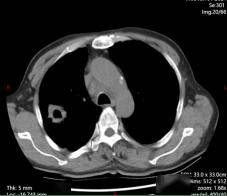

化疗+免疫治疗

化疗+免疫治疗2周期后

2024年7月,老李的右上肺原发灶增大,支气管再次狭窄。我们立刻给患者复查了气管镜。镜下没有新生物,只有黏膜充血水肿;穿刺也只看到变性坏死组织。影像进展、病理阴性,到底是耐药还是感染?我们启动了全院多学科讨论,最后决定:按耐药处理,执行“化疗+免疫”的二线方案。2个周期后,病灶再次显著缩小,疗效评估达到部分缓解。6周期后病灶继续缩小。老李的咳嗽、憋气症状完全消失,吃得好、睡得香,笑称:“我又回到了没得病的状态。”